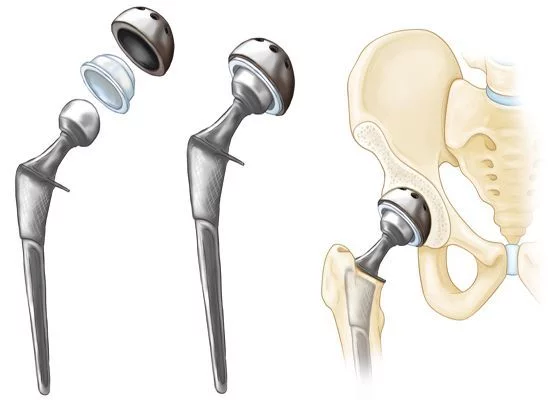

Kalça Protezi Nedir?

Kalça protezi, hasar görmüş eklem yüzeylerinin çıkarılarak yerine metal, seramik veya yüksek dayanımlı plastikten yapılmış yapay eklem yüzeylerinin yerleştirilmesi işlemidir. Amaç; ağrıyı ortadan kaldırmak, hareket kabiliyetini geri kazandırmak ve yaşam kalitesini artırmaktır.